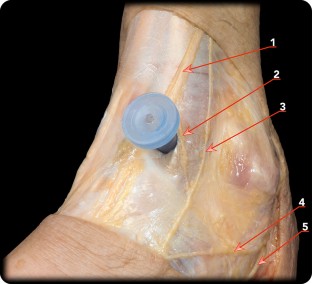

Fig. 1

Fig. 2

Fig. 3

Fig. 4

Fig. 5